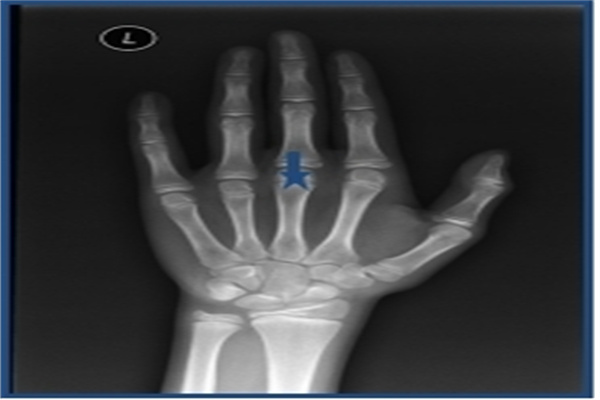

通常需要拍攝兒童的左手手腕部位的X光片,醫(yī)生通過X光片觀察左手掌指骨、腕骨及橈尺骨下端的骨化中心的發(fā)育程度,來確定兒童的骨齡。